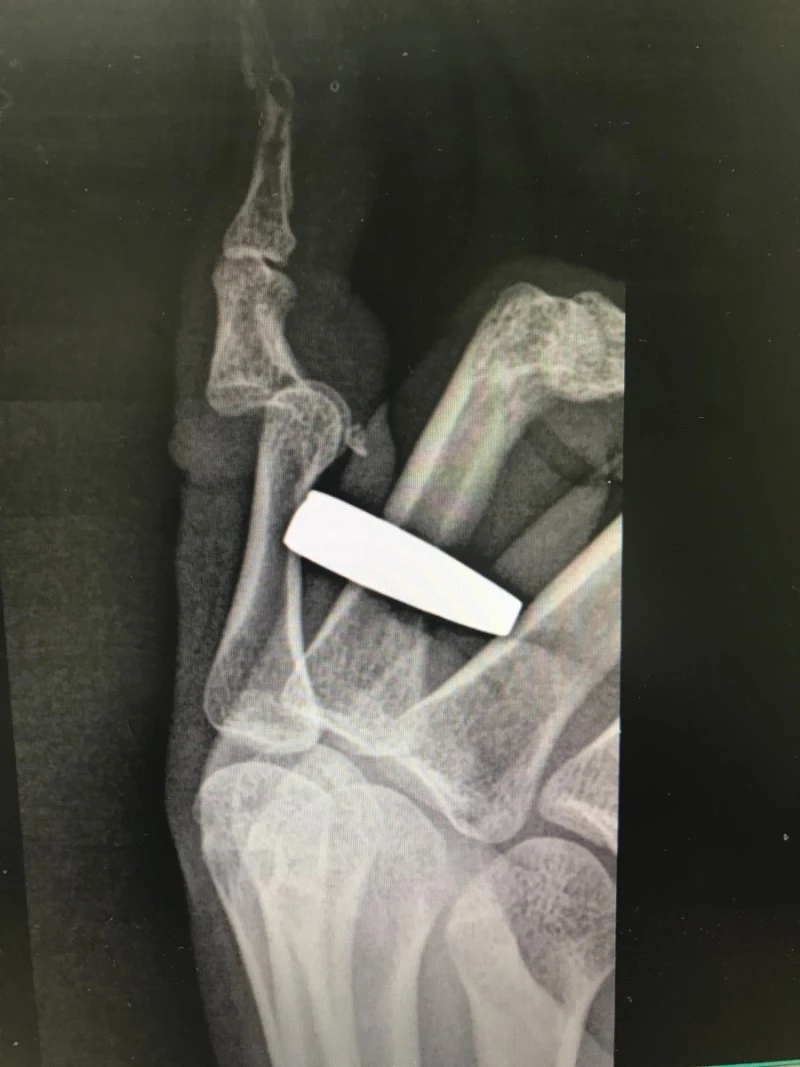

남자친구랑 응급실 들어선 처자. 새끼손가락이 어긋났다며 미간을 찌푸립니다. 어쩌다 손가락이 탈구됐는지 물으니, 가방 들다 손가락이 휘었답니다. 그 가방 제가 들어보니 제법 묵직하네요. 똑딱 단박에 탈구를 정복하고, 가해자 가방을 혼내주었습니다. 명품이 이렇게 위험합니다.